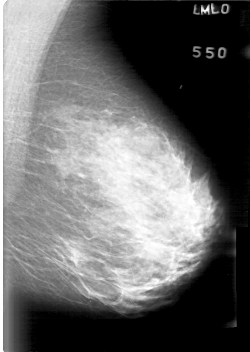

D_4022_1.LEFT_MLO

D_4022_1.LEFT_CC

LEFT_MLO LINES 5266 PIXELS_PER_LINE 3736 BITS_PER_PIXEL 12 RESOLUTION 43.5 NON_OVERLAY